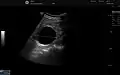

Renal cyst as seen on abdominal ultrasound